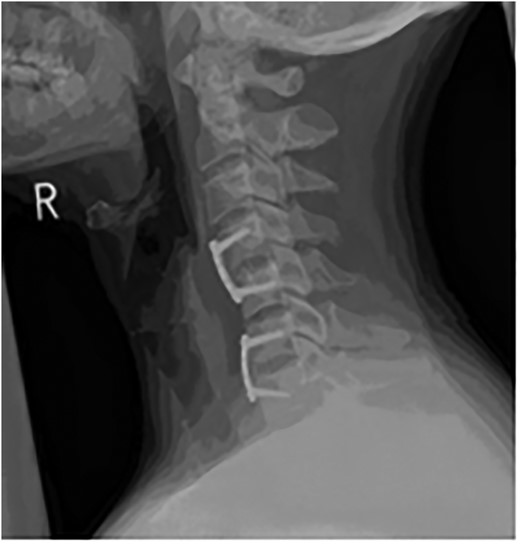

The lateral C-Spine X-ray, taken as part of the trauma series, showed C4–C5 subluxation, grade 1 anterolesthesis and an acute 30° kyphotic deformity at C4/5 level through the disc (Fig. 1).

Lateral C-Spine radiograph showing bilateral C4/5 subluxation.